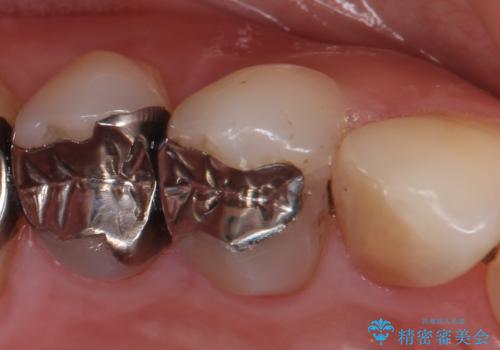

- 右上4番目の歯がなにもしなくてもズキズキ痛むといらっしゃった方の症例です。

検査の結果持続痛も認めたため、虫歯除去後根管治療を行いました。

その後オールセラミッククラウン(エクセレント)による補綴を行いました。